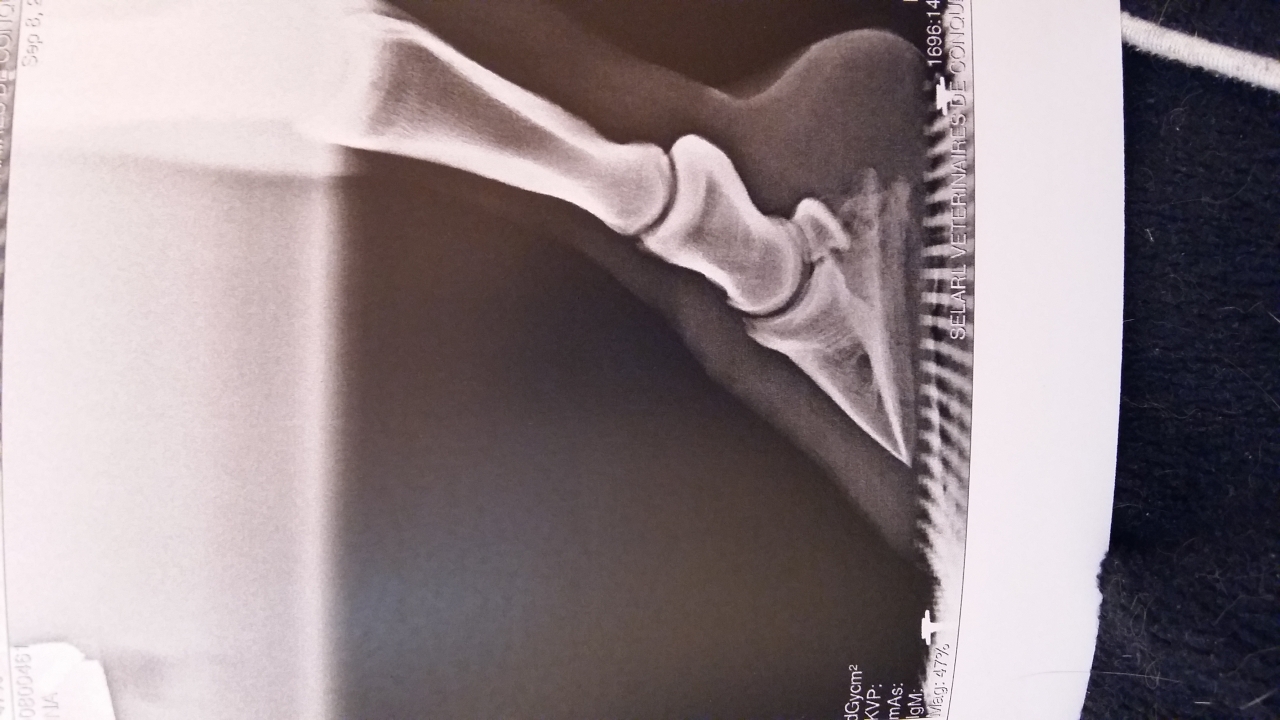

| Dire merci | Bonsoir Bon je suis un peu perdue. On a fait des radios sur ma jument de 18 ans il y a un mois à l'issue desquelles le veto m'a annoncé clairement une sole très très fine sur les 2 antérieurs avec AD légèrement plus encastelé. Il m'a conseillé ferrage avec plaque en cuir ou hipposandales lors des sorties. MAIS clairement la jument a un autre problème qui fait que je vais maintenant arrêter les sorties longues et le travail en carrière (voir le post "bilan clinique avis" . Je ne ferai plus que de courtes balades au pas pour la forme et le moral. Seulement je l'observais au pré l'autre jour ..... elle en bave clairement .... elle ne boite pas comme sur du dur mais elle ne fait pas de folies non plus. Quand j'ai appelé les chevaux ils sont tous arrivés au galop et elle elle a tenté un petit trot mais finalement elle n'a fait que quelques foulées avant de repasser au pas. Certains m'ont dit -pieds nus + hipposandales sur le dur -pieds nus + hipposandales H24 Mais j'ai lu que c'était pas génial de laisser un pied tout le temps enfermé dedans ?? -ferrure légère orthopédique Oui c'est quoi ? -ferrure classique +plaque comme dit le veto Pour rappel voici les radios : ![]() ![]() Autre rappel:ça fait 5 ans que la jument est pieds nus. Merci !! |

| Dire merci | Vu les radios, c'est de la "maltraitance" de la laisser sans fer. Elle doit souffrir au quotidien. Alors une paire de fer au moins pour l'éloigner du sol sera une bonne chose. Après a voir si tu veux investir dans de l'orthopédie ... mais au moins des fers avec un bon roll.... |

| Dire merci | Enfin là on est au delà de la sole fine (comme pour ma jument), c'est PATHOLOGIQUEMENT fin. C'est pour ça que je n'ai pas foncé tête baissée dans "on ferre". Il faut absolument soulager la jument (c'est l'erreur que j'ai fait, en pensant que le temps ferait bien les choses... nawak), mais il faut trouver un moyen de faire pousser la sole. Même ferrée, avec ses quelques mm de sole, le moindre cailloux lui fait mal. Et suspendre P3 avec le fer sans sole en dessous n'est pas plus beaucoup plus confortable ou à court terme... Donc vois : - éventuelles carences - Parage à plat trop invasif - Manque de vascularisation (ça passe par le mouvement) - juste la vieillerie : booster avec de la biotine? - pour soulager : PHW plutôt que les chaussures. Je les ai posé moi même après une première pose, ça tient plusieurs semaines sans soucis. Le temps va être en ta faveur, les terrains vont mollir. Après des semaines de sensibilité, ma jument prend difficilement le trot et le galop (elle n'a pas encore confiance je pense) sauf si sol magique genre sable. Je lui laisse le temps. Elle marche d'un très bon pas, c'est déjà une victoire. |